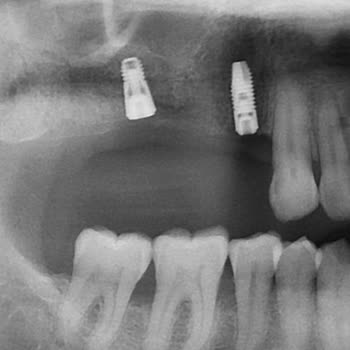

Straumann marka implant yaptırdım fakat Straumann temsilcisi G*** Ö***** yüzünden üzerine protezleri taktıramıyorum. Kendisi gerekli olan ara parçalar için önce diş hekimi vasıtası ile ek ücret istetti, daha sonra biz müdürüne tesadüfen ulaşıp durumu sorunca ücret çıkmadığını gördük ve ödemedik. Bu ...